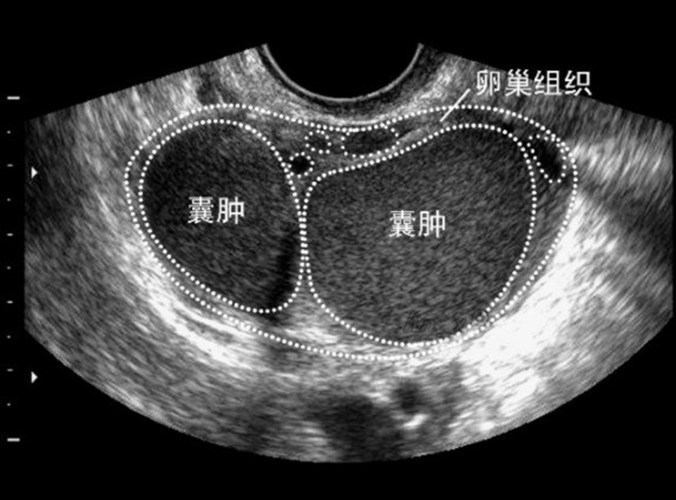

(1)、影像学检查:阴道和腹部B型超声检查能够确定巧克力囊肿的位置、大小、形状和囊内容物。